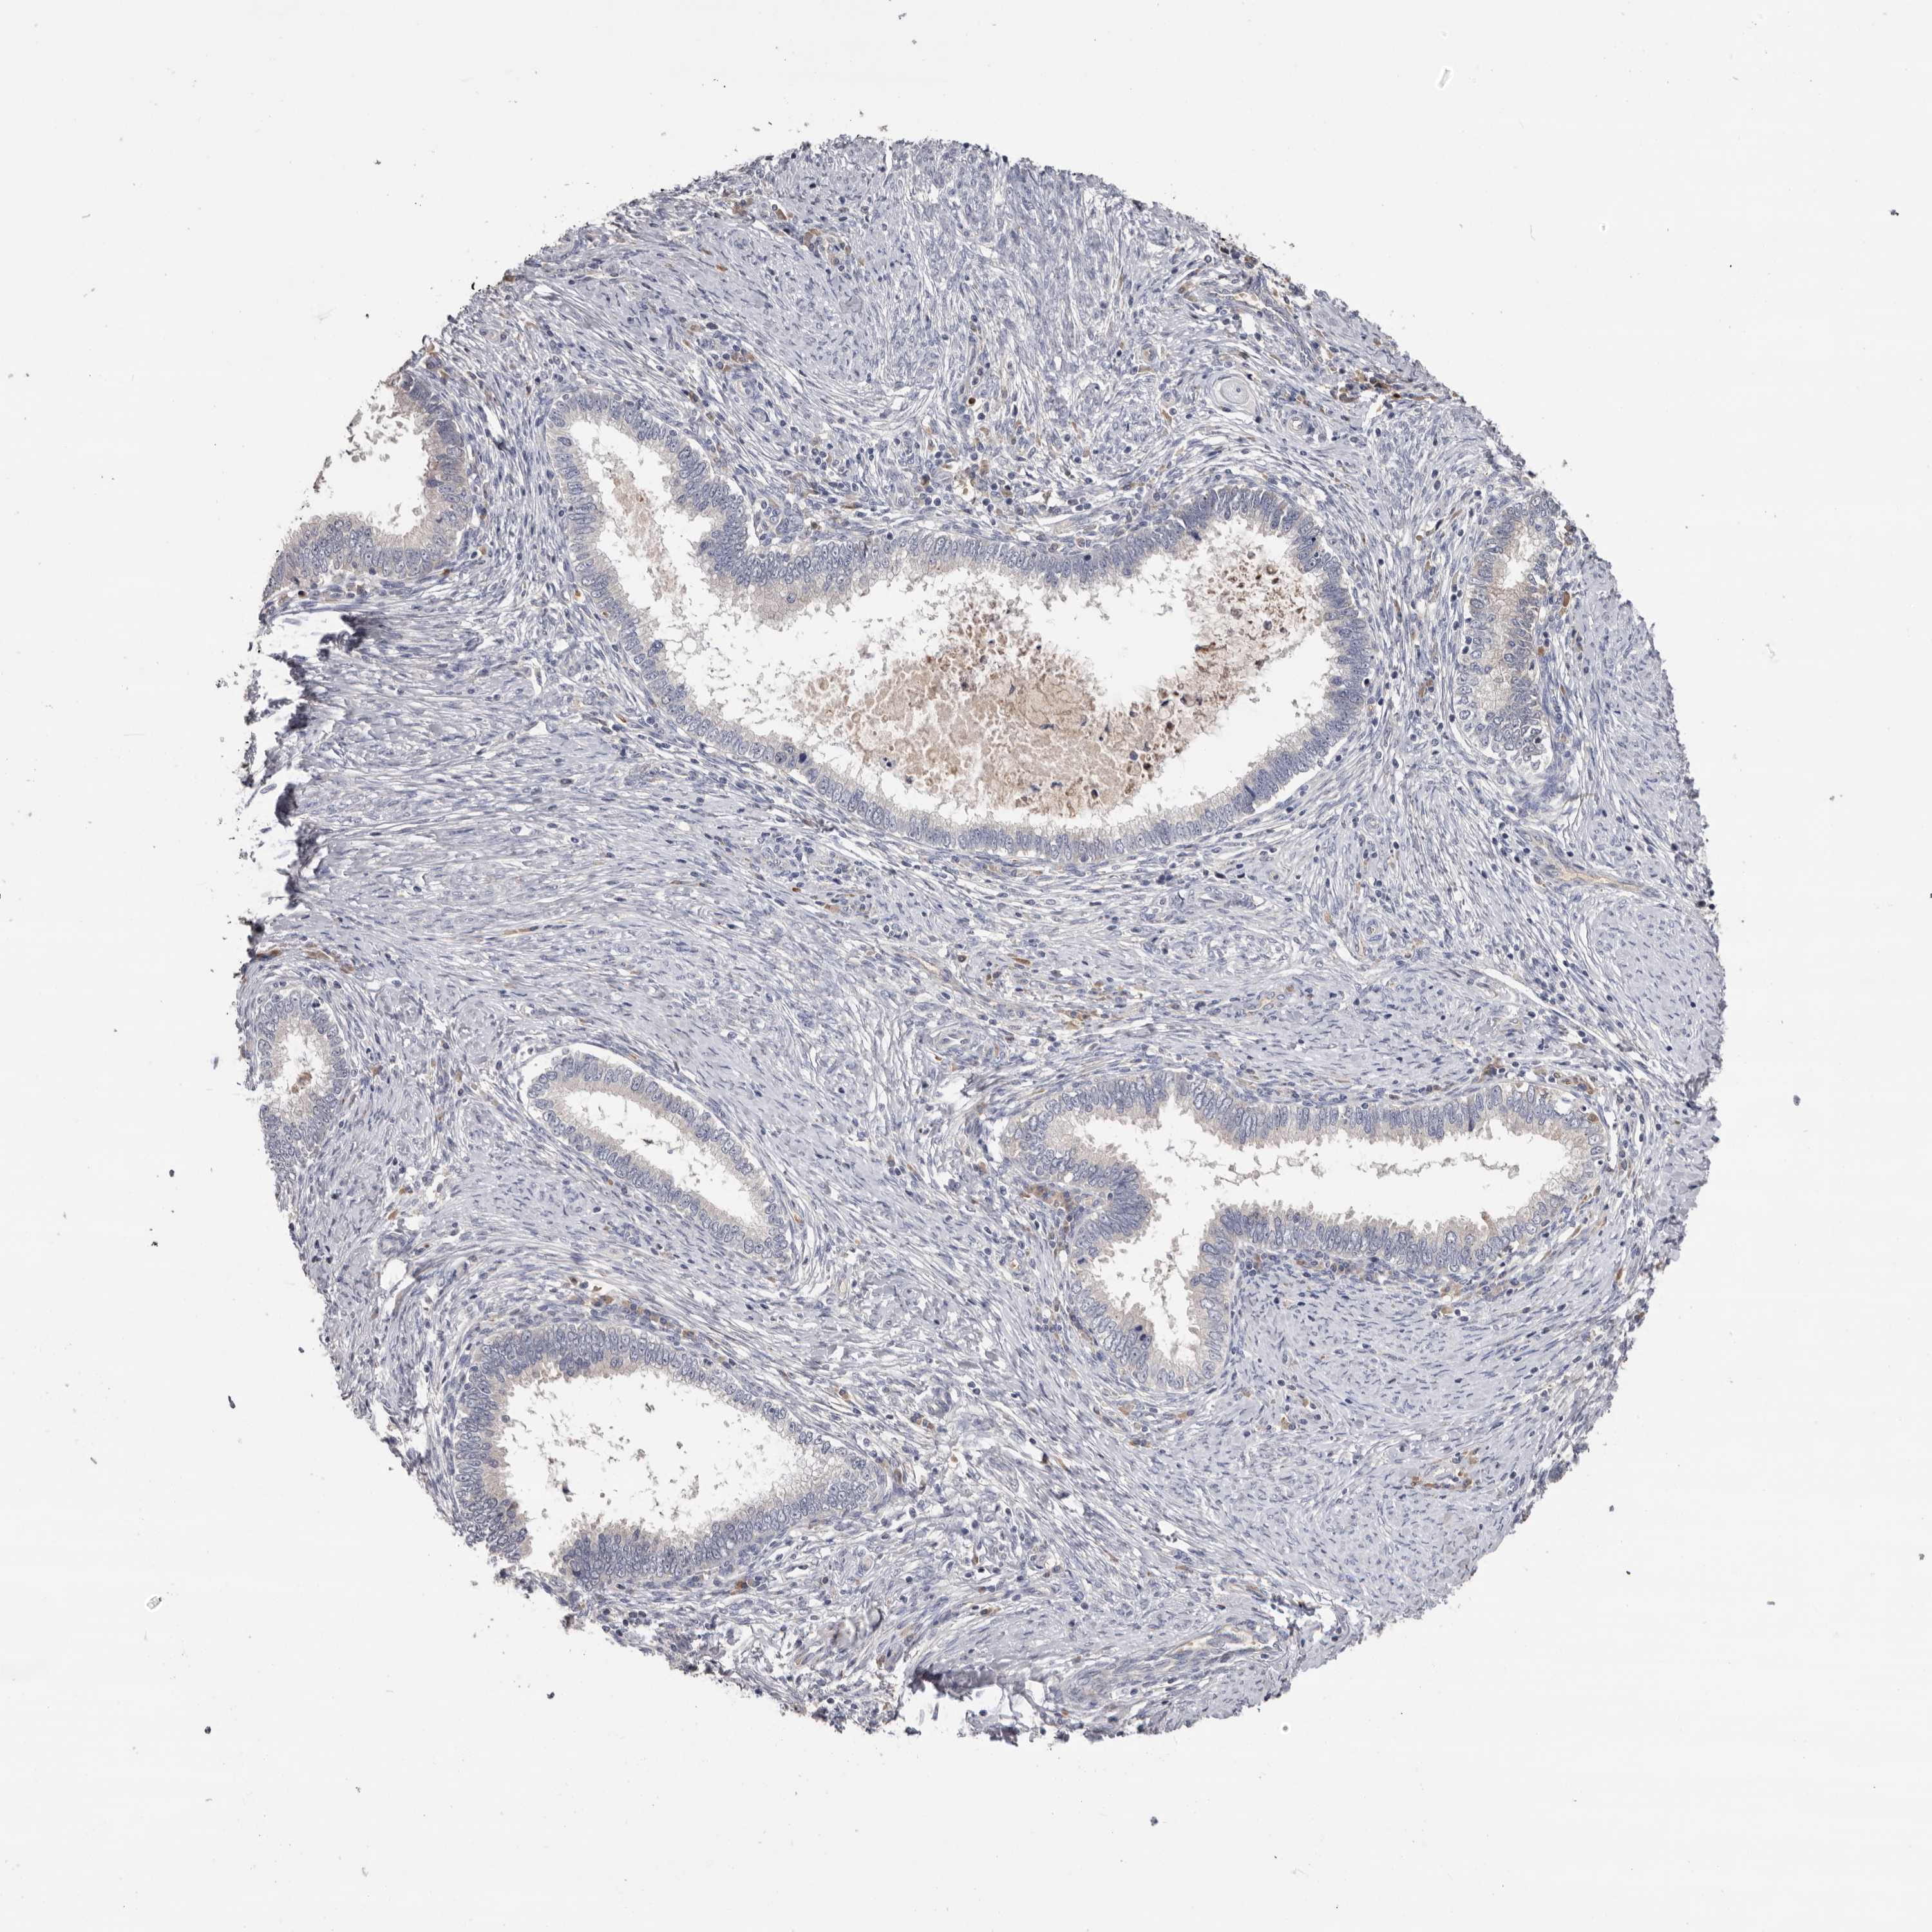

CERVICAL CANCER - Protein expressioni

A mouse-over function shows sample information and annotation data. Click on an image to view it in a full screen mode. Samples can be filtered based on level of antibody staining by selecting one or several of the following categories: high, medium, low and not detected. The assay and annotation is described here.

Note that samples used for immunohistochemistry by the Human Protein Atlas do not correspond to samples in the TCGA dataset.

Antibody stainingi

Antibody staining in the annotated cell types in the current human tissue is reported as not detected, low, medium, or high, based on conventional immunohistochemistry profiling in selected tissues. This score is based on the combination of the staining intensity and fraction of stained cells.

Each image is clickable and will lead to virtual microscopy that enables deeper exploration of all samples and also displays staining intensity scores, fraction scores and subcellular localization as well as patient and tissue information for each sample.

Antibody HPA023081

Antibody HPA023103

Antibody HPA024795

Adenocarcinoma, NOS